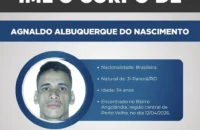

PAÍS | De tão incomum, a história de um paciente de Manaus, de 54 anos, mereceu um relato de caso publicado na plataforma científica International Journal of Surgery Case Reports na última quarta-feira (6).

O paciente procurou o serviço médico da capital do Amazonas relatando dores de estômago, náuseas e dificuldade de evacuação. Disse que apresentava os sintomas há dois dias, mas não forneceu detalhes sobre o que poderia ter causado a condição.

Ao realizarem um exame de raio-X, os médicos encontraram um peso de dois quilos, de cerca de 20 centímetros de comprimento, como os que são usados em academias de ginástica para exercícios de braço, dentro do homem.

O haltere estava entre o reto e o intestino grosso do paciente, que, depois do exame, admitiu ter introduzido o peso de academia no corpo para obter satisfação sexual.

Para retirar o objeto do paciente, a equipe sedou o homem. Inicialmente, os médicos tentaram puxar o halter com uma pinça cirúrgica, mas, como não foi possível manejá-lo, a retirada teve que ser feita por um dos cirurgiões com as mãos. Após três dias de internação, o paciente recebeu alta e se encontra bem.

No relato de caso, os médicos lembram da importância de os profissionais de saúde fazerem uma abordagem cuidadosa em situações assim. De acordo com eles, por causa do constrangimento, é frequente que o paciente não revele a origem do problema.